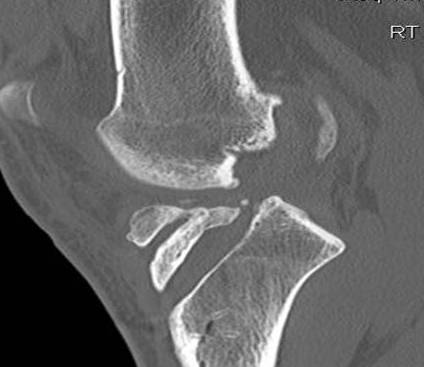

Coronal MRI can see ACL stump remnant, graft not intact. First sagittal confirms tunnel lysis.

Second demonstrates that femoral tunnel is sufficiently posterior